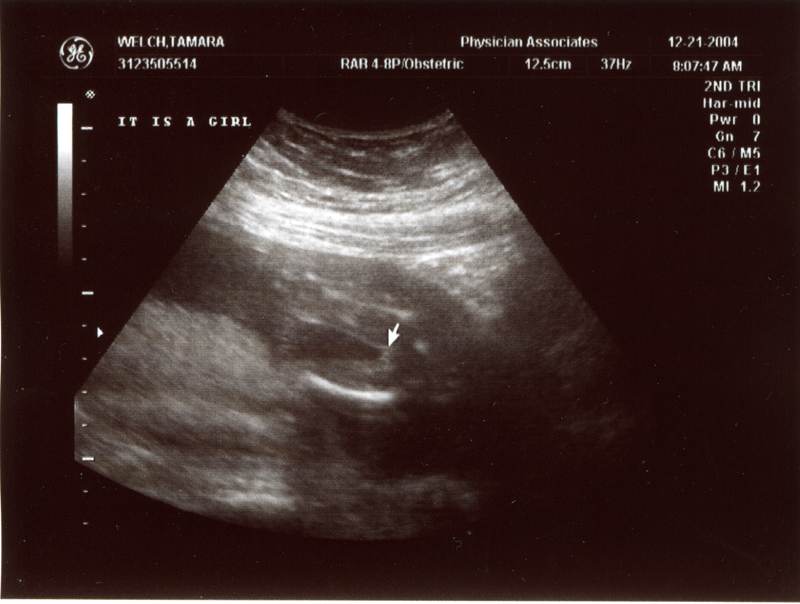

December 21, 2004 - We

had our second ultrasound and found out the sex of the baby. It's

a GIRL! We could see her moving around and see the heart beating.

We also heard the heartbeat during the doctor's visit. The heartbeat

is 150 bpm and the weight is 9 oz. Click on the images below to

see the pictures from the ultrasound. In the image titled "It's

a Girl" you can tell it's a girl because there is nothing

between the legs (the legs are in a "V" shape). We are

thrilled that everything is going well. We are planning to name

her Megan Storey Welch.